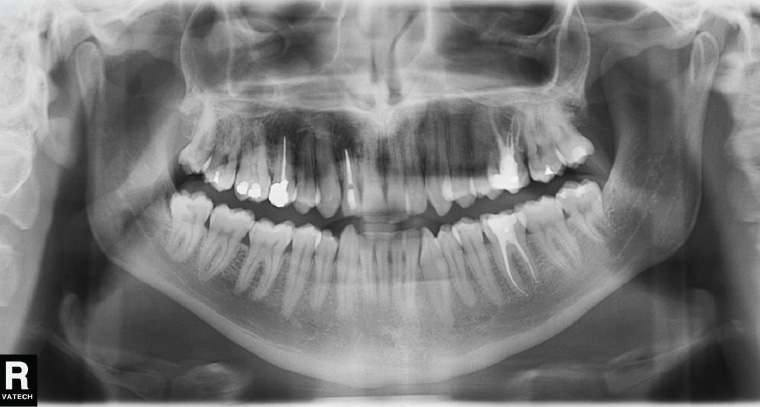

OPG Dental X-Rays: Precision Panoramic Imaging for Better Diagnosis An OPG (orthopantomogram) is one of the most valuable tools in modern dental imaging, providing a comprehensive view of both jaws, all teeth, and the surrounding bone structures in a single scan.At 3Beam Imaging Centre in Harley Street, we perform digital OPG dental X-rays using high-resolution…